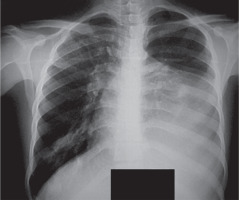

A 22-year-old man was admitted to Ghaem teaching hospital, Mashhad, Iran with 3 months history of dyspnea on exertion and chest heaviness. He had no other chest, constitutional symptoms or signs of autoimmune disorders. On physical examination the only abnormal finding was complete absence of vesicular breath sounds in the left hemithorax. Posteroanterior chest radiograph revealed a huge fat density obscuring the left heart and mediastinal border (Figure 1).

Figure 1

Chest radiograph of the case showing huge mass with fat density in left hemithorax obscuring left heart border